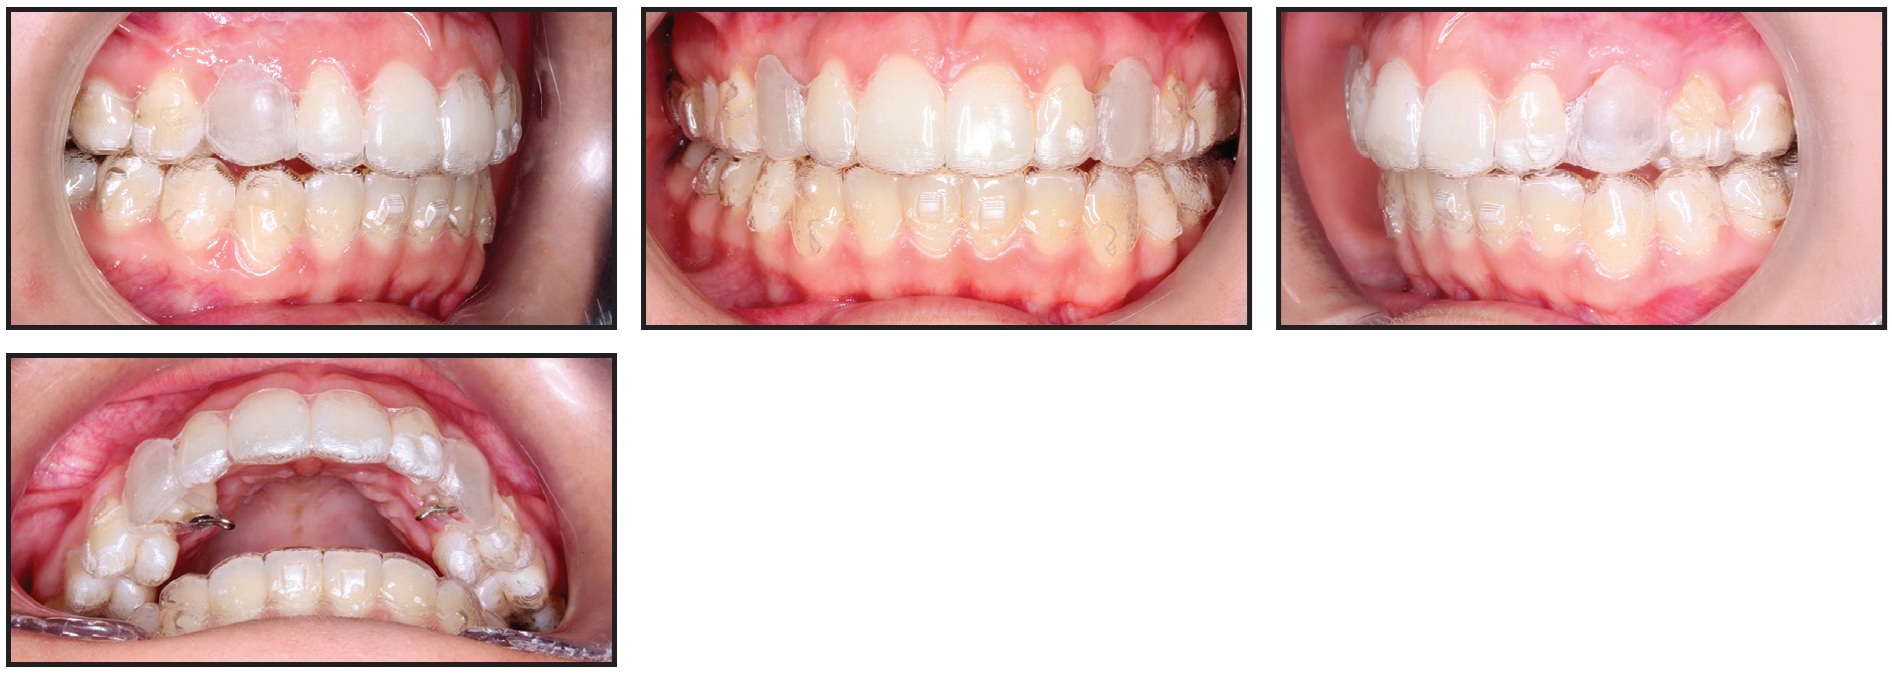

After a total 36 months of treatment, the alignment and torque of the canines were corrected, with both sides in occlusion (Fig. 6). Gingivectomies of both canines were performed to obtain even gingival margins.

Fig. 6 Case 1. Patient after three years of treatment, showing well-aligned canines.

After 30 months of active treatment, the maxillary and mandibular arches were well aligned, the posterior crossbite was corrected, the overjet and overbite were within normal ranges, and bilateral Class I canine and molar relationships were obtained (Fig. 10). At the end of treatment, a gingivectomy of the canine was performed to align its soft-tissue contours with those of the adjacent teeth.

Fig. 10 Case 2. Patient after 30 months of treatment, showing alignment of impacted upper right canine, correction of posterior crossbite, and normalization of overjet and overbite.